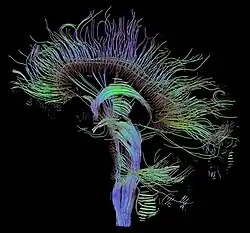

Magnetic resonance imaging (MRI) is a common form of biological data visualization used to form pictures of internal biological processes. Different settings of radiofrequency pulses and gradients result in different image appearances; these combinations are known as MRI sequences. A particularly notable subset of MRI is magnetic resonance angiography, which is a group of techniques used to image arteries and veins. MRI's imaging utility is further expanded upon by diffusion MRI and functional MRI, which can be used to capture neuronal tracts and blood flow respectively.

Diffusion MRI further relies on diffusion tensor imaging (DTI), which measures water molecule diffusion and directionality, and diffusion basis spectrum imaging (DBSI), which extracts multiple anisotropic and isotropic diffusion tensors.[39][40] Functional MRI relies on blood-oxygen-level dependent (BOLD) contrast, which measures the proportion of oxygenated hemoglobin in specific areas of the brain; this allows it to measure and model brain activity based on blood flow.[41] Further MRI techniques include saturation pulses (used to reduce motion artifacts), gradient echo (such as dynamic contrast enhancement), spin echo, and diffusion weighting (a signal contrast generation method based on differences in Brownian motion).[42][43][44]